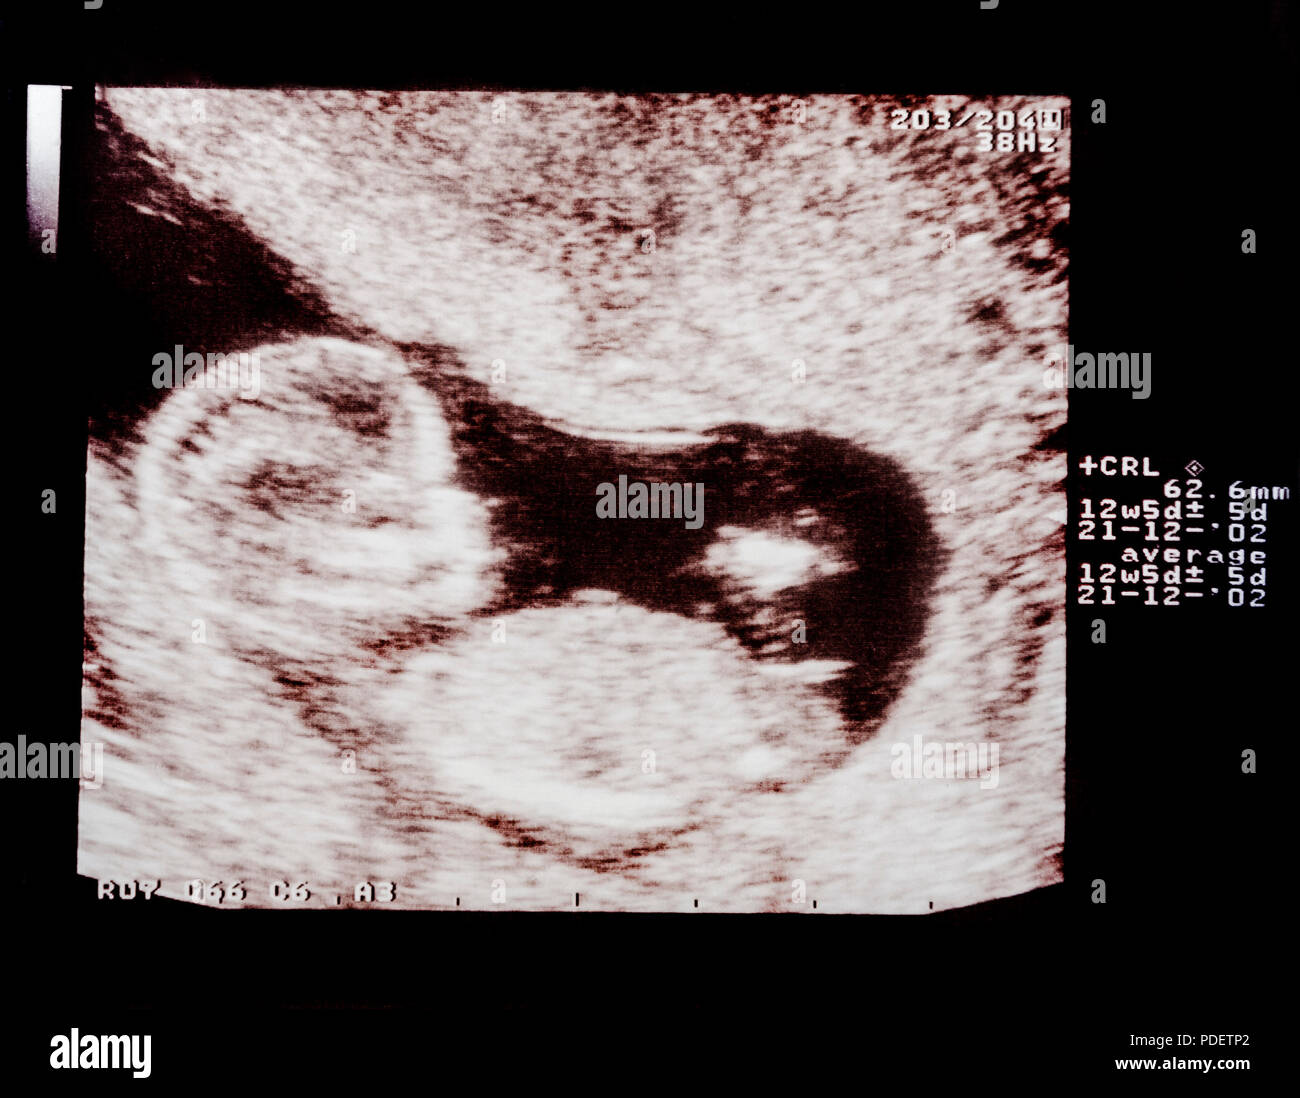

First trimester antenatal ultrasound scan at 3 month pregnancy health …

Ultrasound images of embryo or fetal development at various stages of …

3 Month Pregnant: What to Expect?